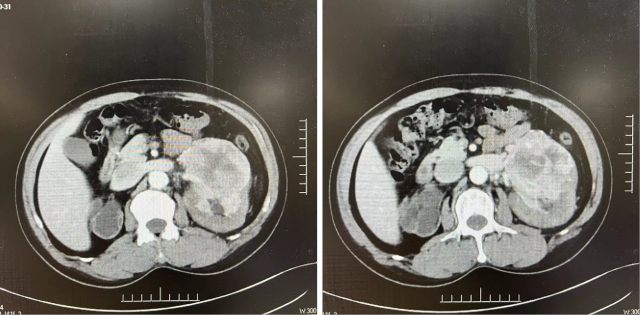

影像学检查

2023-11-08:

2024-02-28: